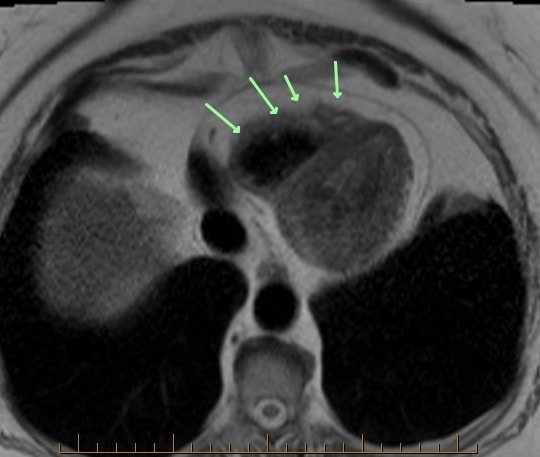

Where is the squeeze play here on axial T1 cardiac MRI?

The squeeze play here is a fatty tumor compressing the superior vena cava. The vena cava is normally round. Here, it appears squeezed or slit-like (second image, arrow). This could lead to superior vena cava syndrome. Surveillance recommended every 6 months. The third MR image shows signs of right ventricular dysplasia. The anterior right ventricle is lobulated, irregular and exhibits sparse fat signal.